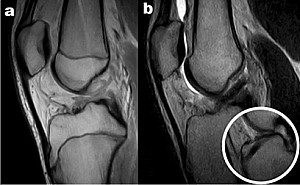

Figura 1: Lesione di LCA in paziente di 7 anni con immaturità scheletrica

Le lesioni del LCA in età pediatrica rappresentano meno del 5% di tutte le lesioni dell'LCA, ma la loro incidenza è aumentata di circa il 2-3% all’anno negli Stati Uniti, grazie sia a una maggiore esposizione sportiva dei giovani sia ai progressi nelle tecniche di imaging (Figura 1) [1]. In passato, molti specialisti rimandavano la ricostruzione del LCA fino al completo sviluppo scheletrico, temendo danni alle cartilagini di accrescimento. Tuttavia, il trattamento conservativo tende a causare instabilità articolare con elevata incidenza di lesioni meniscali secondarie (fino al 70% dei casi) che predispongono a precoce artrosi [2]. D’altra parte, la ricostruzione eseguita troppo precocemente, se non condotta con attenzione, può provocare arresto di crescita o deformità assiali. Nonostante le linee guida emesse da organismi internazionali, manca un consenso univoco riguardo a indicazioni, tempistiche e tecniche chirurgiche [3]. Al fine di colmare questa lacuna, proponiamo un modello gestionale che unisce le migliori evidenze disponibili all’esperienza clinica, indirizzando le decisioni terapeutiche negli atleti giovani con cartilagini aperte.